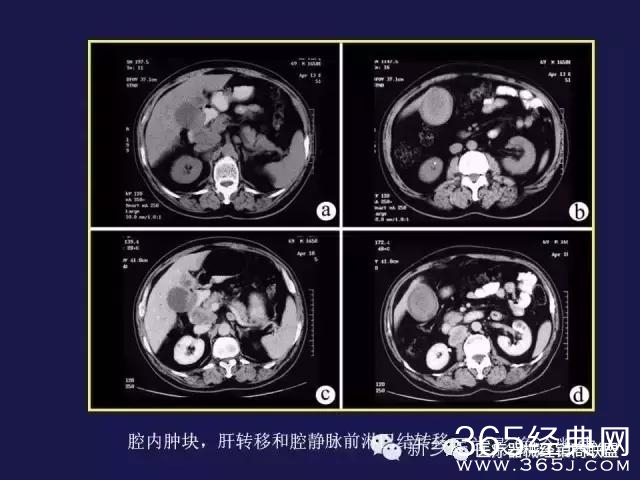

CT、MRI很难?NO,今日我们一起来学习一下如何读CT、MRI!

内行看门道: